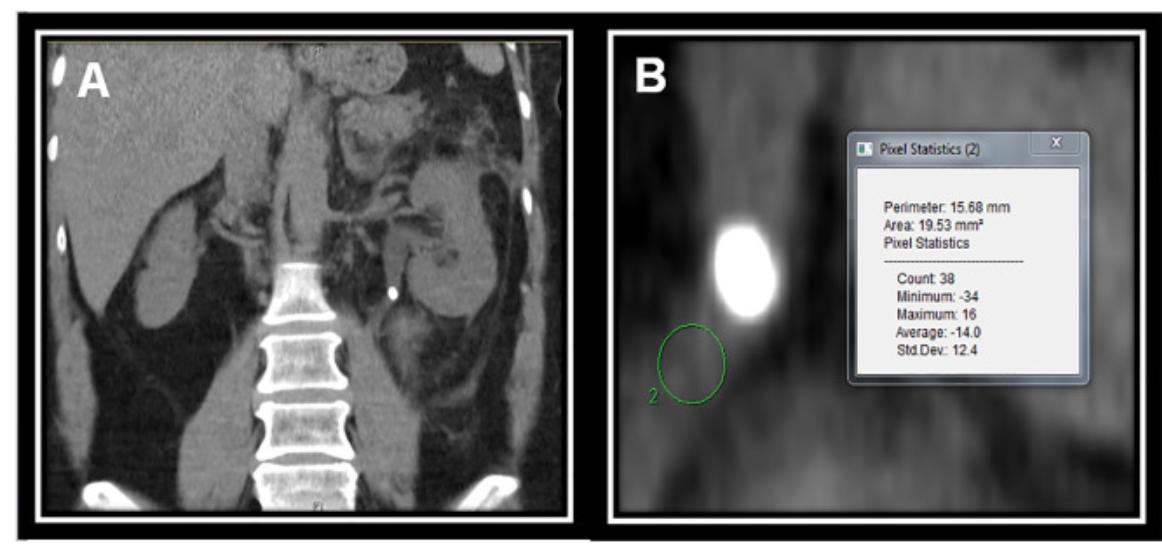

Can preop CT be used to predict impacted stones? Our model indicates HU under stone can predict impaction. Mantu Gupta, M.D. sciencedirect.com/science/articl…

Can preop CT be used to predict impacted stones? Our model indicates HU under stone can predict impaction. <a href="/MantuGuptaMD/">Mantu Gupta, M.D.</a> sciencedirect.com/science/articl…